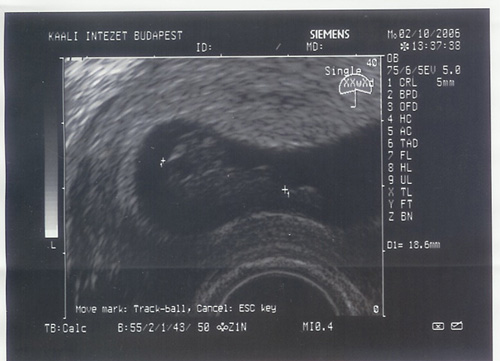

Íme a pocak, amiben Emili lakik.

Íme a pocak, amiben Emili lakik.  Timi még pocaklakó!

Pocaklakó kívülről és belülről is

Pocaklakó kívülről és belülről is  Teljes szívvel és lélekkel melletted állunk és már nagyon várjuk,h. ez a kis Csöppség világra jöjjön.